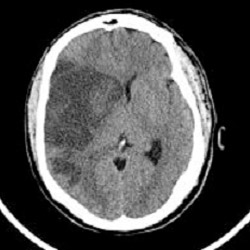

Cells of brain do not have any reserves of energy of their own; they depend on fresh supply of oxygenated arterial blood. If the blood supply is disrupted even for few minutes, brain cells die and the function controlled by them is lost. Stroke is caused by disruption of blood supply to areas of the brain, either due to a Clot ('Thromboembolic Stroke') or due to Bleeding from any of the arteries supplying blood to brain ('Hemmorhagic Stroke' or Brain Hemorrhage). Diabetes is a hypercoagulable state and blood clots form easily. Atherosclerosis of arteries further makes them narrow and arteries tend to block more easily. Stroke may be preceded by so called Transient Ischemic Attack (or TIA), which is a forewarning of an incumbent stroke due to a small thrombus blocking an artery but getting dissolved subsequently. The symptoms of TIA may be similar to those of a stroke but are milder and transient, resulting in prompt recovery (with in 24 hours)

Stroke is an 'Acute Emergency' thus the patient suffering from a stroke should be immediately rushed to a superspeciality hospital where all the facilities are available. There are some treatments (rtPA or alteplase) available for acute stroke (thrombo-embolic), but have to be administered in a short period of time (preferably < 3 hours) after the onset of stroke to give maximum benefit. High Blood glucose levels during or after stroke may cause another acute complication of Diabetes-Hyperosmolar Hyperglycemic Syndrome, which may further complicate the management of stroke. In case of brain haemorrhage ('Haemmorhagic Stroke'), the treatment is to control high blood pressure and any other cause if present. Sometimes even brain surgery may be required.